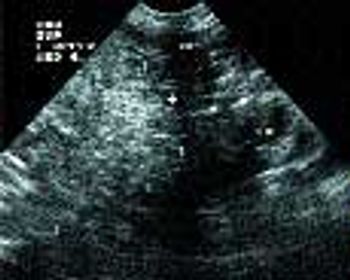

Signalment: Canine, Greyhound, 2.5 years old, female spayed, 65 lbs. Clinical history: The dog has a persistent urinary tract problem ? hematuria for at least one year according to the owner. The dog improves with antibiotics, but once finished, hematuria starts again. Therapy has included Clavamox.